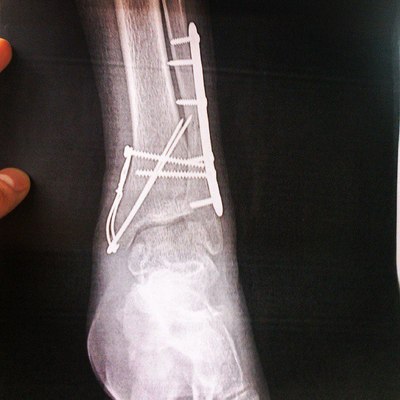

Дтп, переломов была куча, радует, что зажило как на собаке, ну не без помощи врачей естественно)